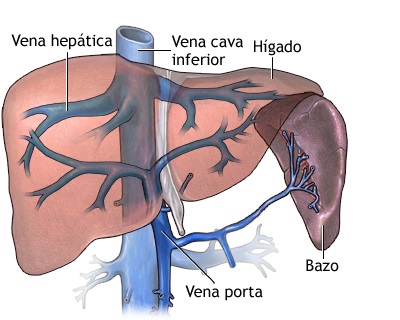

La vena porta hepática, un componente vital del sistema circulatorio, se destaca por su papel central en la irrigación hepática y las modificaciones que experimenta la sangre en su trayecto a través del hígado. Su anatomía específica se caracteriza por actuar como un enlace entre dos redes capilares fundamentales.

La primera de estas redes capilares es periférica y visceral, siendo la vena porta hepática su representante. Esta red recoge sangre venosa proveniente de órganos abdominales como el estómago, intestinos, bazo y páncreas. La sangre, cargada con los productos de desecho y nutrientes absorbidos durante la digestión, es dirigida hacia el hígado para su procesamiento.

La segunda red capilar se encuentra en las extremidades de las ramas terminales de la vena porta hepática dentro del propio hígado. Aquí, en este intrincado entramado capilar hepático, ocurren modificaciones significativas en la sangre. El hígado actúa como una «glándula de secreción interna», realizando funciones metabólicas esenciales que incluyen la regulación de la glucosa, la síntesis de proteínas y la desintoxicación de sustancias.

La vena porta hepática se forma mediante la convergencia de dos venas principales: la vena mesentérica superior, que se extiende verticalmente, y la vena esplénica, que tiene una disposición transversal. Este punto de convergencia refleja la integración de flujos sanguíneos de dos regiones anatómicas fundamentales: los órganos del tracto digestivo y el bazo.

La vena porta hepática culmina su trayecto en el porta hepático, donde se divide en dos ramas, una derecha y otra izquierda. Esta bifurcación marca el punto final de su recorrido y tiene implicaciones críticas en la distribución de la sangre venosa hacia las diferentes áreas del hígado. Esta disposición anatómica asegura una adecuada irrigación del órgano y la ejecución eficiente de sus funciones metabólicas y fisiológicas.